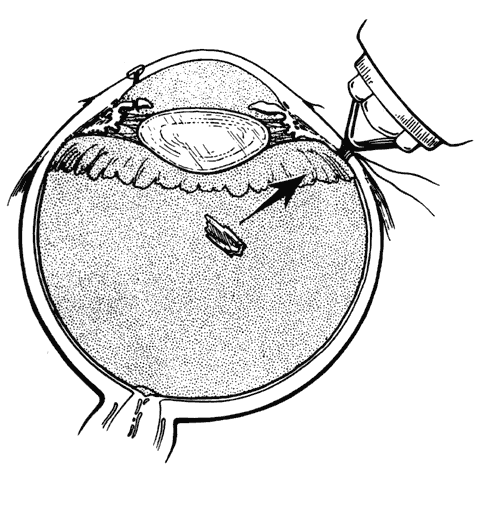

Retinal breaks are created at the time of nonpenetrating blunt injuries3 in 10% to 20% of eyes.3–6 Retinal dialyses are most frequent2–6 and are most often found in the lower temporal (Fig. 2) and upper nasal periphery (Fig. 3).2 Large irregular breaks at the point of impact of blunt trauma are less common but are equally characteristic of nonpenetrating injuries (see Fig. 3).2,7,8 Horseshoe and opercular tears of the equatorial retina (see Fig. 3) are associated with the more characteristic breaks in 25% of eyes.2 Small round holes in atrophic retina at the point of traumatic impact and macular holes (see Fig. 3) are infrequently observed after ocular contusion.2,8

Fig. 2. Large lower temporal dialysis at the point of impact of blunt trauma. (Cox MS: Retinal breaks caused by blunt nonperforating trauma at the point of impact. Trans Am Ophthalmol Soc 78:418, 1980)

Retinal dialyses in the lower temporal quadrant are often very large, with gaping posterior edges located well behind the equator (see Fig. 2). They are caused by injuries impacting the lower temporal portion of the globe that result in the dissolution and disappearance of retinal tissue.8 In contrast to nontraumatic giant retinal tears with rolled-over retina, they respond favorably to scleral buckling without vitrectomy. A scleral buckle is indicated for smaller dialyses that can be closed with an explant of reasonable size. Very large breaks, as illustrated in Figure 2, are best treated with vitrectomy, gas tamponade, and laser, as recommended for nontraumatic giant retinal tears, rather than with a very large scleral buckle.